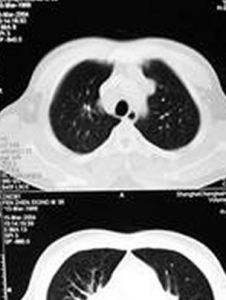

(2)肺內改變:早期為肺泡炎表現,胸片上呈腺泡結節小斑片狀陰影,以兩側肺門為中心向外擴散,結節影小者可呈毛玻璃樣改變。中期則有肺間質浸潤,表現為肺紋理增厚、粗亂以及網狀結節狀陰影。晚期除有結節樣改變外,尚有肺間質纖維化,病變甚者可見肺大皰。

①胸片顯示雙側肺門及縱隔對稱性淋巴結腫大‘偶見單側肺門淋巴結腫大)。伴或不伴有肺區域網路狀、結節狀、片狀陰影,必要時參考肺部CT進行分期;

提高對肺結節病的認識和診斷符合率。方法:對1990~2007年經病理確診為結節病8例患者的臨床誤診資料作回顧性分析。結果:肺結節病臨床表現不典型,胸部 X線及CT常表現為肺門增大,以雙側肺門腫大為主,易誤診為肺結核或腫瘤。經纖維支氣管鏡活檢或皮膚黏膜、淋巴結活檢可確診。肺結節病多見於青中年人,女性發病率高,臨床症狀不典型,在診斷上要結合臨床表現、胸片以及纖維支氣管鏡檢、皮膚黏膜、淋巴結活檢進行病理檢查。